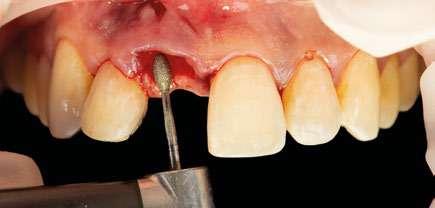

na paciente de 35 años (Figura 1) fue remitida a la Clínica de Odontología Reconstructiva de la Universidad de Zúrich debido a una infección crónica en el diente 11 y con expectativas estéticas muy altas. El diente 11 había sufrido un trauma hace 10 años y había sido tratado con multiple endodoncias sin éxito. El diente presentaba un absceso bucal (Figura 2), una bolsa periodontal aislado de 9 mm, y una ausencia de la tabla vestibular ósea (Figura 3). El diagnóstico se estableció como una fractura radicular vertical, lo que resultó en un pronóstico pobre. El plan de tratamiento consistió en una extracción combinada con preservación alveolar, colocación de implante diferido con injerto de tejido conectivo, una corona cerámica implantosoportada en 11 y una nueva carilla de cerámica para el diente 21.

El diente 11 fue extraído (Figura 4), seguido por la preservación alveolar. Se realizó un injerto pediculado de espesor parcial rotado del paladar (Figura 5), junto con una membrana de colágeno reabsorbible, un xeno-injerto bovino y cianoacrilato sellando al alveolo (Figura 6). La provisionalización consistió en un puente adhesivo de resina con dos alas de metal. El alveolo se dejó cicatrizar durante 6 meses, después de los cuales se tomó una impresión digital así como un escáner CBCT (Figura 7). Se llevó

a cabo una planificación digital para una cirugía guiada de implante en una posición protéticamente ideal (Figura 8). El implante 11 se colocó completamente guiado a través de una férula (Figura 9). Las dimensiones del reborde alveolar eran ideales para la colocación del implante en una posición atornillada (Figura 10), al igual que la calidad del hueso cicatrizado. Un injerto de tejido conectivo subepitelial fue estabilizado ocluso-bucalmente al implante (Figura 11) y el puente adhesivo fue recementado (Figura 12). Después de 3 meses de cicatrización, se realizó una restauración provisional y se acondicionó adecuadamente para dar forma al perfil de emergencia, imitando el del diente adyacente (Figura 13). Después de una fase provisional, se tomó una impresión analógica individualizada para el implante 11 y el diente 21 (Figura 14). El laboratorio fabricó una corona implantosoportada de zirconio con cerámica estratificada para el 11 y una carilla laminada feldespática para el diente 21 (Figura 15). Ambas restauraciones fueron colocadas en la paciente y mantenidas. La paciente quedó muy satisfecha con el resultado estético de las restauraciones (Figuras 16, 17). Después de 2 años, el implante permanece saludable con el hueso marginal estable (Figura 18) y una buena calidad y cantidad de tejido blando.